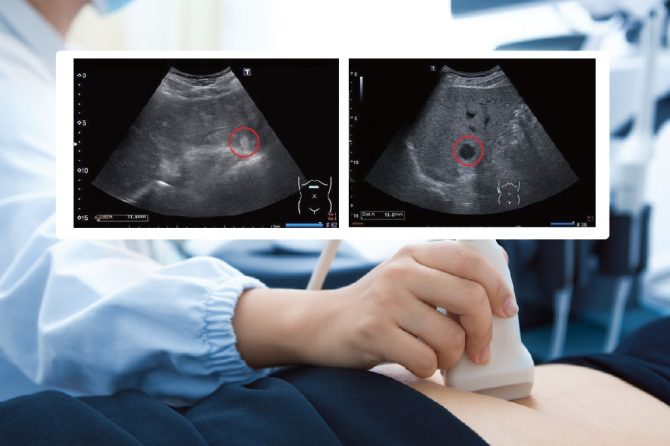

肝臟是腹腔內最大的實質性內臟,最常在超音波檢查下發現的病灶是肝臟腫瘤,又分為良性及惡性。

1. 肝囊腫

就是常說的水泡,是一個含清澈液體的囊狀結構,囊腫可很大也可以很小,通常毫無症狀且不影響肝臟功能,也無藥物可讓肝臟囊腫消失。特別大的水泡有可能壓迫周邊器官產生症狀。隨著年紀增長,囊腫數目可能會增加或有變大的跡象,很小的水泡也有可能被吸收消失,患者不必緊張擔心,只要定期追蹤和平相處即可

2. 血管瘤

是血管異常增生而形成的腫瘤,發生率大約在2-5%之間,能否發現有賴檢查醫師的細心觀察,大部分的血管瘤呈現高回音影像,也就是影像上屬於較白的成像,確診血管瘤最好是在不同的觀察切面都能看到影像。由於小血管瘤沒有症狀也不會影起肝臟功能的變化,因此只需定期追蹤大小變化即可,極少數的血管瘤會緩慢長大。對於無法確認性質或有長大的跡象,可安排腹部電腦斷層或核磁共振攝影來鑑別診斷。